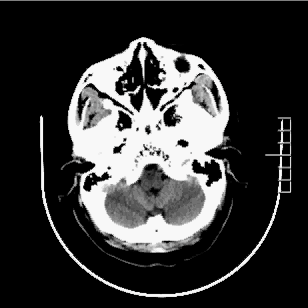

影像诊断

入院CT

病历夹什么径技·第152期|串联营病历夹:川陕大营_https://www.jmylbn.com_新闻资讯_第57张

病历夹什么径技·第152期|串联营病历夹:川陕大营_https://www.jmylbn.com_新闻资讯_第58张

<<滑动查看下一张图片>>